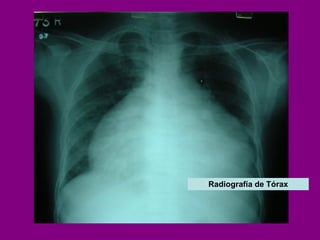

Aumento de tamaño de la silueta cardíaca  en presencia de derrame pericárdico importante  ( > 250 ml), con forma de «cantimplora».   Radiografía de Tórax

Radiografía de Tórax